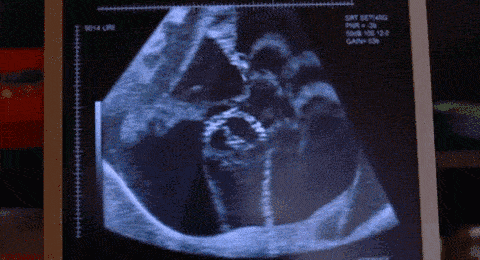

孕期胎动频繁,和胎儿性格有关吗?有哪些科学依据?

孕期胎动频繁 , 和胎儿性格有关吗?有哪些科学依据?

孕期胎动频繁 , 我觉得跟胎儿的性格有一定的关系 , 但是胎动频繁也会受其他因素影响 。

如果胎儿的性格比较文静 , 那么胎动会比较柔和 , 幅度小 , 动作轻柔 , 胎动由慢到快 , 由弱到强 。 有些胎儿比较爱睡觉 , 那么胎动就相对比较少 , 即使偶尔有胎动 , 也会是打嗝 , 像鱼儿游动的感觉 。

如果胎儿的性格比较好动 , 那么胎动就会比较粗暴 , 幅度大 , 动作有力 , 胎动很快 , 很强烈 , 孕妇会感觉到突然的疼痛 。 胎动出现的次数多 , 持续的时间长 。 有些胎儿 , 尤其是男胎 , 喜欢在妈妈睡觉的时候捣蛋 。